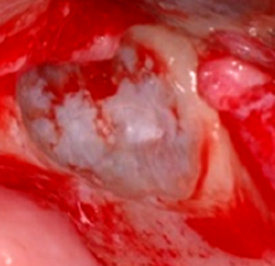

상악동 점막(Schneiderian membrane)은 점막 거상 후 골이식을 가능하게 해주는 해부학적 구조물로 천공이나 찢어짐이 없다면 골이식재를 지지해주는 역할을 하기 때문에 상악동 골이식술의 성공과 실패에 많은 영향을 준다. 육안으로 상악동 점막은 코점막에 비해 혈관분포가 적어 청백색을 띠며<그림 15>, 현미경학적으로는 섬모를 가진 위중층원주상피로 이루어져 있다<그림 16>.

△그림 15. 상악동 점막

상악동 점막을 골점막(mucoperiosteum)이라 불리기도 하는데 조직학적으로 상악골과 하악골의 골막과는 다르고 상악동점막과 주변골사이에 골모 세포가 없기 때문에 아직 논란의 여지가 있다. 다만, 최근 여러 연구를 통해서 상악동 점막에 의한 골유도능력이 관찰되어 보고되기도 하였다. 실험을 통해 상악동 점막의 거상하여 골이식재 없이 거상 부위에 혈액과 임플란트만 식립하고 경과 후 현미경으로 분석한 결과, 임플란트 주변으로 신생골이 형성된 것을 관찰할 수 있었다(Clinical Implant Dentistry and Related Research, Volume 8, Number 1, 2006)<그림 17, 18>.

△그림 17. 상악동 점막 거상 후, 혈액이식 및 임플란트 식립

△그림 18. 상악동 점막에 의한 임플란트 주변 신생골 형성0

앞으로도 상악동 점막에 대한 연구가 더 필요하나, 확실한 것은 건강하고 손상되지 않은 상악동 점막은 상악동 골이식술 예후에 매우 긍정적인 영향을 미친다는 것이다.